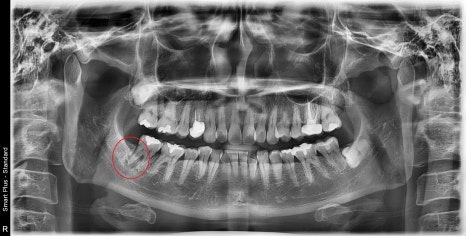

타치과에서 오른쪽 아래 어금니 발치 진단을 받으셨습니다.

과거에 잠시 통증이 있었지만 현재는 증상은 없지만

치아 주변 뼈가 많이 소실된 것을 볼 수 있습니다.

CT를 찍으면 더 확실하게 볼 수 있습니다.

뿌리 주변의 검은색으로 보이는 곳들이 염증으로 인한 치조골이 소실된 것입니다.

방사선 사진상에서도 뿌리에 금이 갔을 때 보이는

전형적인 치조골 소실 양상입니다.

빨간 원으로 표시된 부분을 보시면 육안으로도 보이는 명확한 crack line이 보이실 겁니다.